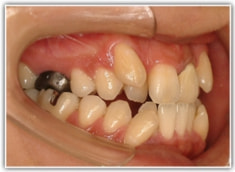

治療後(2年3ヶ月後)

歯根のパラレリング(平行性)が獲得されております。

下顎8番は、両側抜歯済みです。